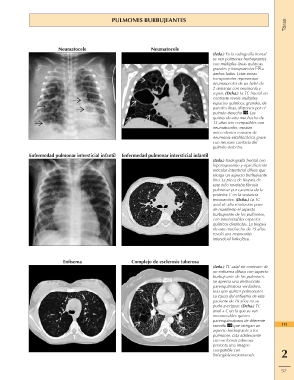

PULMONES BURBUJEANTES Tórax

Neumatocele Neumatocele (Izda.) En la radiografía frontal

Enfermedad pulmonar intersticial infantil se ven pulmones burbujeantes

con múltiples áreas quísticas

grandes y transparentes a

ambos lados. Estas zonas

transparentes representan

neumatoceles de un bebé de

2 semanas con neumonía y

sepsis. (Dcha.) La TC frontal sin

contraste revela múltiples

espacios quísticos, grandes, de

paredes finas, dispersos por el

pulmón derecho . Los

quistes de este muchacho de

12 años son compatibles con

neumatoceles; existían

antecedentes remotos de

neumonía estafilocócica grave

con necrosis cavitaria del

pulmón derecho.

Enfermedad pulmonar intersticial infantil (Izda.) Radiografía frontal con

hiperexpansión y opacificación

reticular intersticial difusa que

otorga un aspecto burbujeante

fino. La pieza de biopsia de

este niño revelaba fibrosis

pulmonar por carencia de la

proteína C en la sustancia

tensioactiva. (Dcha.) La TC

axial de alta resolución pone

de manifiesto el aspecto

burbujeante de los pulmones,

con innumerables espacios

quísticos diminutos. La biopsia

de este muchacho de 15 años

reveló una neumonitis

intersticial linfocítica.

Enfisema Complejo de esclerosis tuberosa (Izda.) TC axial sin contraste de

un enfisema difuso con aspecto

burbujeante de los pulmones. 115

Se aprecia una destrucción

parenquimatosa verdadera, 2

más que quistes pulmonares.

La causa del enfisema de este 57

paciente de 16 años no se

pudo averiguar. (Dcha.) TC

axial + C en la que se ven

innumerables quistes

parenquimatosos de diferente

tamaño que otorgan un

aspecto burbujeante a los

pulmones. Esta adolescente

con esclerosis tuberosa

presenta una imagen

compatible con

linfangioleiomiomatosis.